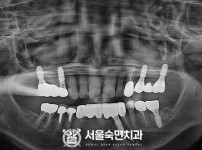

임플란트-전후사진1

치과를-선택할-때-꼭-확인하세요-서울숙면치과-임플란트-전후사진